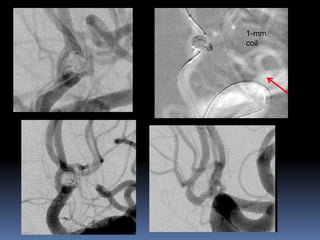

Very small aneurysms

? Near the neck rupture/lobule

Catheter reposition

1-mm coil

Branch from aneurysm-Overinflationtechnique